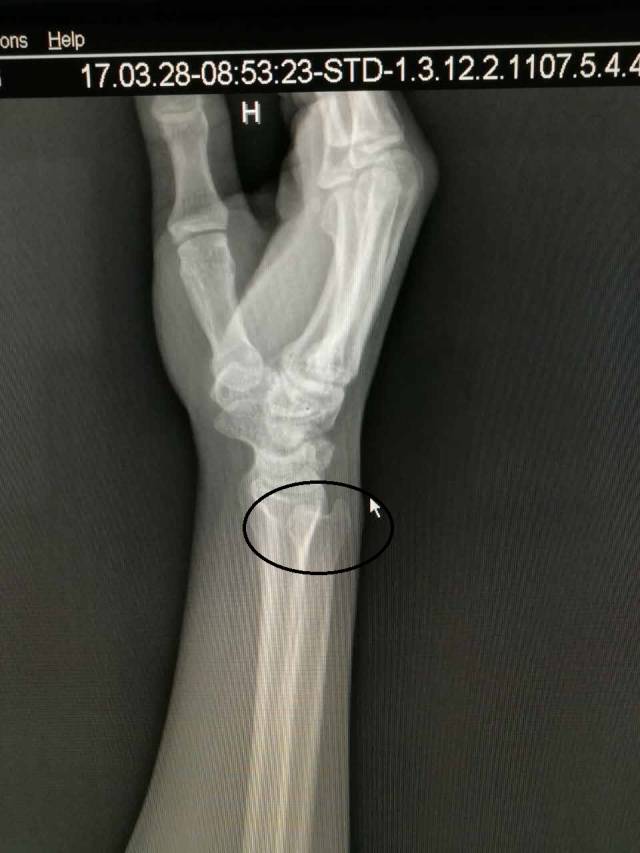

(图中所打圈的位置就是下尺桡关节)

对于没有经验的人来说,很多人会以为损伤是撞到“麻经”了,丝毫没有觉察,其实已经下尺桡关节脱位了。其实下尺桡关节脱位的伤害不亚于骨折,如何自测有没有下尺桡关节脱位呢,笔者告诉大家一定要注意以下4点: